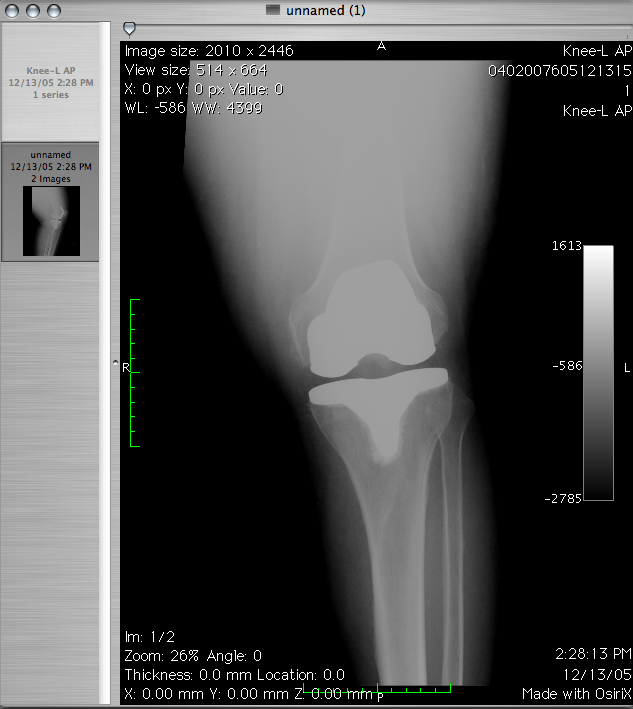

Jedną z szybciej rozwijających się dziedzin jest rehabilitacja. Nie wiedzieliśmy kiedyś jak wielki potencjał w …

Jedną z szybciej rozwijających się dziedzin jest rehabilitacja. Dawniej nie wiedzieliśmy, jaka moc w niej …

Jedną z szybciej rozwijających się dziedzin jest rehabilitacja. Dawniej nie wiedzieliśmy, jaka moc w niej …

Rehabilitacja obecnie rozwija się niezwykle szybko. Dawniej nie wiedzieliśmy, jaka moc w niej drzemie. Dziś …